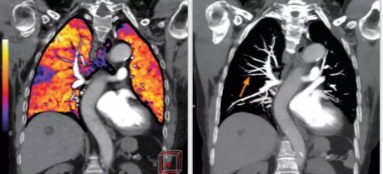

相比傳統成像方式,肺部柔性減影技術通過人工智能,對平掃數據和CT肺動脈血管掃描數據進行智能比對,解碼并識別各個器官(肺、氣管、肺動脈、肺靜脈、主動脈等)的空間位置,并在三維空間中進行體素級的柔性配準,從而極大提升了不同序列數據的空間位置的一致性。通過肺部柔性減影技術可得到肺強化碘圖,可以顯示出傳統CTPA圖像看不到的小栓塞病變,提高了栓塞檢出率,其結果甚至可與SPECT吻合。

肺智能柔性減影成像功能發(fā)現亞段肺栓塞